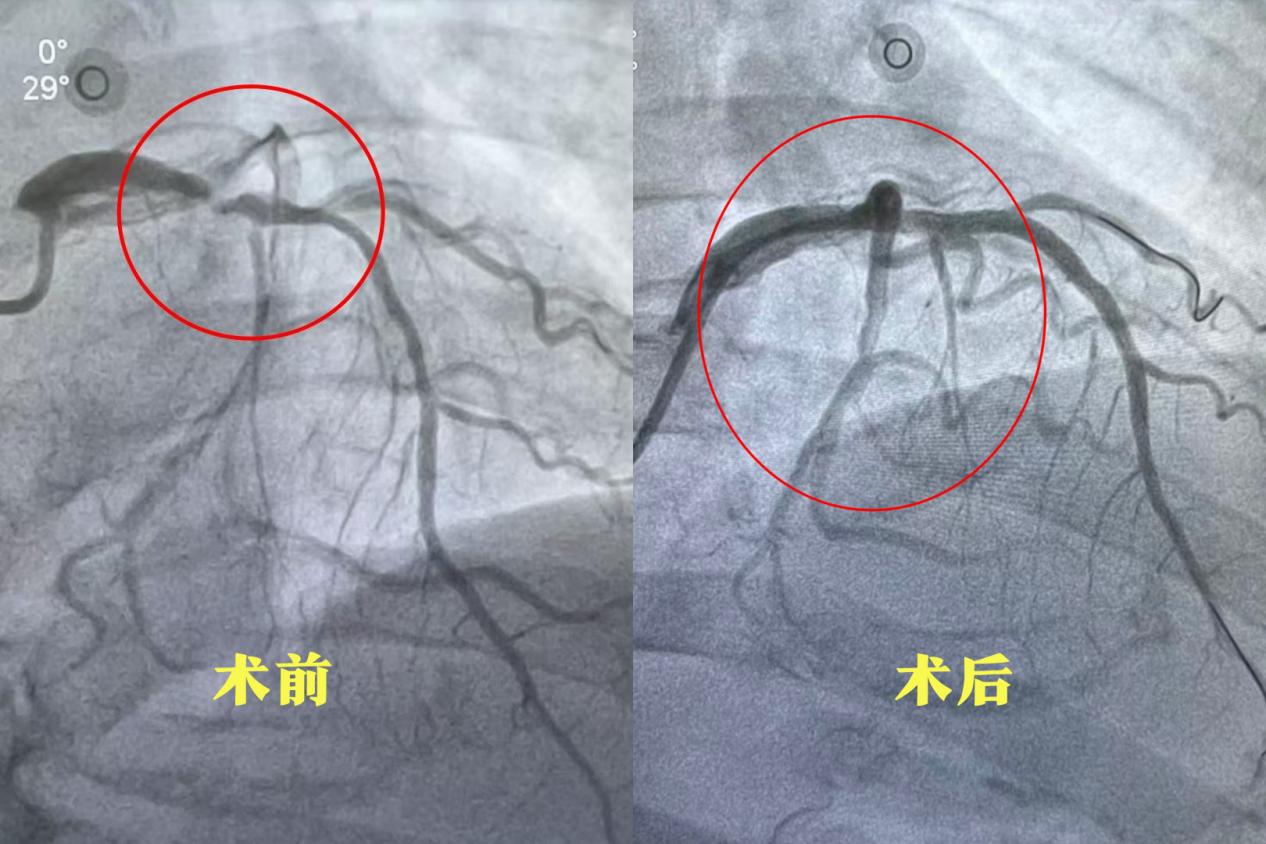

另一例患者郝先生发病超24小时就诊,冠脉造影显示冠脉多发重度狭窄,右冠脉远段狭窄达95%,且血管走形迂曲、合并严重钙化,介入治疗难度极高。面对挑战,介入团队凭借熟练的技术与密切配合,历经两小时精准操作,成功完成右冠脉血运重建。